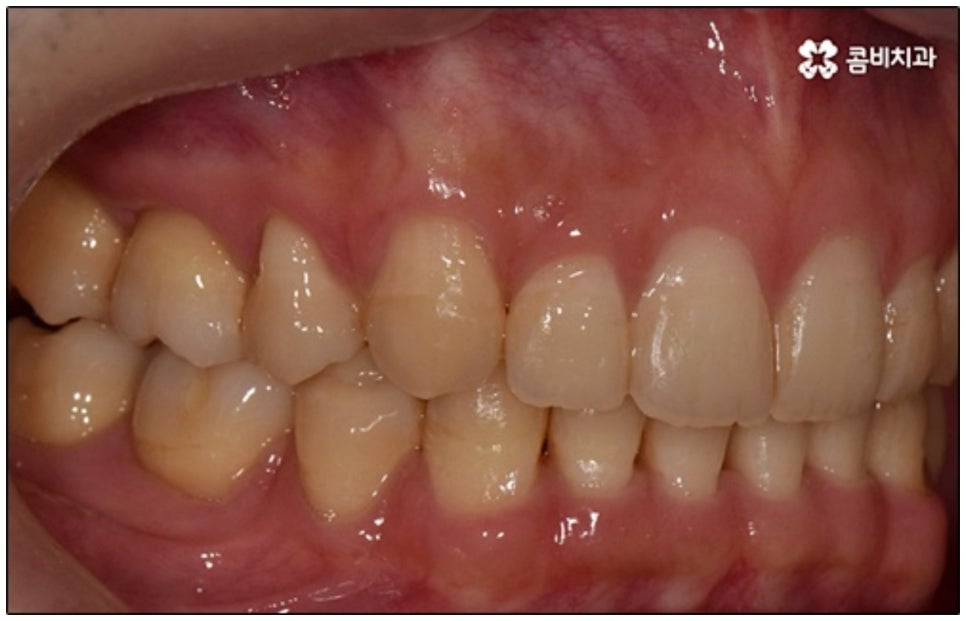

말씀드린 것과 같은 다양한 이점들이 있기 때문에 현재 본원의 교정 환자분들은 대부분 클리피씨교정 장치를 이용하여 치료를 진행하고 있습니다. 사진 역시 돌출입 교정을 위해 발치 후 클리피씨교정 장치를 이용하신 환자분의 케이스인데 시간이 지날수록 점차 앞니가 자연스럽게 들어가고 위아래 교합이 정확하게 맞아가는 것을 확인하실 수 있을 거예요.